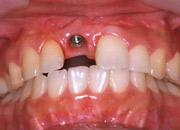

CASE.1(前歯部にインプラントを埋入した症例)

インプラントを埋入し、仮歯を装着した後、骨に結合するのを数ヶ月待ちます。 |

セラミックのクラウンを装着して完了。新しい歯は装着感も機能も天然歯と同様になります 。 |